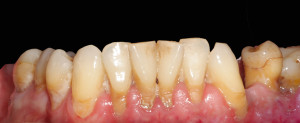

Widać wyraźnie, że kamień i gruba warstwa płytki bakteryjnej wywołał stan zapalny dziąseł – są przekrwione, i opuchnięte. Higienistka wykonała skaling naddziąsłowy skalerem EMS, wypiaskowała zęby piaskiem Air-Flow Plus oraz wypolerowała pasta polerską. Po zabiegu różnica wyglądzie zębów jest diametralna: zdjęcie 2, zdjęcie 5.

Naszym celem jednak jest nie tylko ładny wygląd zębów ale wyleczenie stanu zapalnego dziąseł, a to nie będzie możliwe bez dokładnego wyedukowania pacjenta. Higienistka przeprowadziła szczegółowy instruktarz prawidłowej metody szczotkowania – pokaz na modelu i samodzielna próba pacjenta na własnych zębach. Pacjent nauczył się również stosowania szczoteczek międzyzębowych, będących w jego przypadku niezbędnym akcesorium higienicznym ze wglądu na szerokie przestrzenie miedzyzębowe. Zalecone zostały środki pomocnicze – Eludril do płukania, pasta Elgydium Anti-Pacjent spotkał się z nasza higienistka jeszcze dwa razy, w celu dokonania kontroli i ewentualnego doczyszczenia. Na drugiej wizycie kontrolnej dziąsła pacjenta wyglądały tak: zdjęcie 3, zdjęcie 6. Komentarz jest chyba zbędny: różnica widoczna gołym okiem, dziąsła są zdrowe, bladoróżowe, bez opuchlizny. Gratulujemy!!!